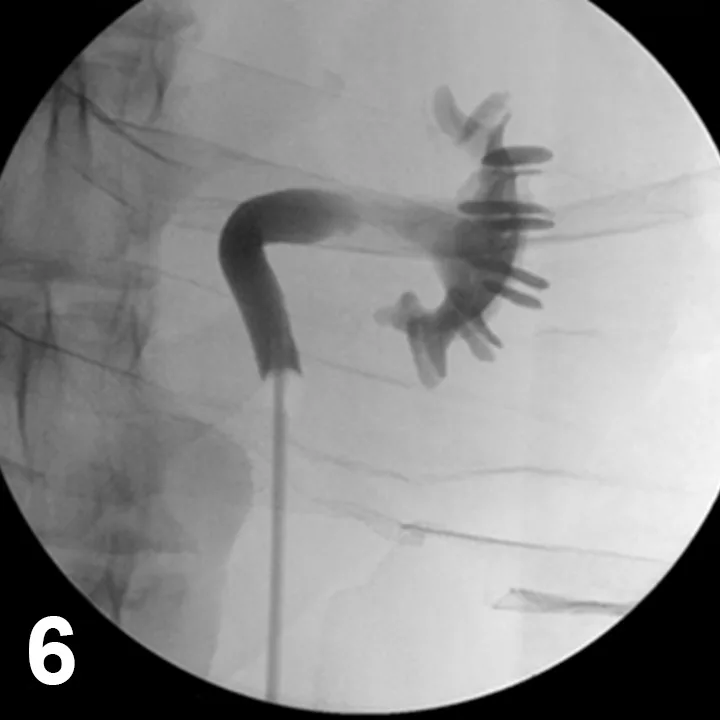

A more applicable procedure for essential renal hematuria is sclerotherapy for topical ureteral infusions (Figure 6). This has been performed in veterinary medicine and is most useful when the ureter is too small to allow ureteroscopic access.4

Figure 6. Retrograde ureteropyelogram during sclerotherapy in a female dog with idiopathic renal hematuria in dorsal recumbency during cystoscopy and fluoroscopy.

The procedure is performed with cystoscopic and fluoroscopic guidance in which a cauterizing sclerosing agent is carefully infused into the renal pelvis to stop the bleeding. The success rate is over 75%, and the procedure avoids the need for ureteronephrectomy. Between 25% and 33% of dogs will have bilateral benign renal bleeding with this condition, so nephrectomy should be avoided when possible.